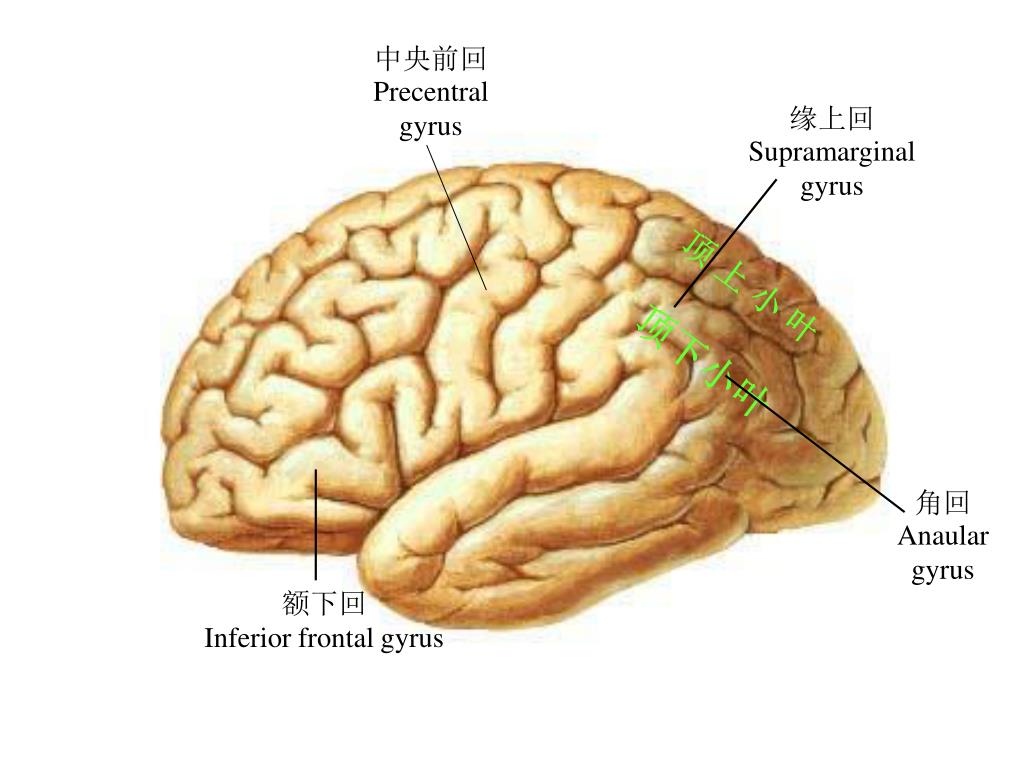

Супрамаргинальная извилина: Функции и Исследования